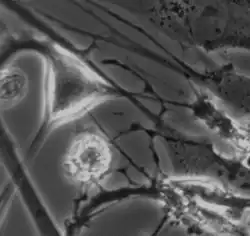

Interstitial cell of Cajal shown in the myenteric plexus of a mouse embryo